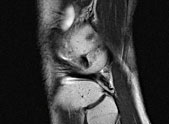

Leber- und Knochenmetastasen

bei Brustkrebs